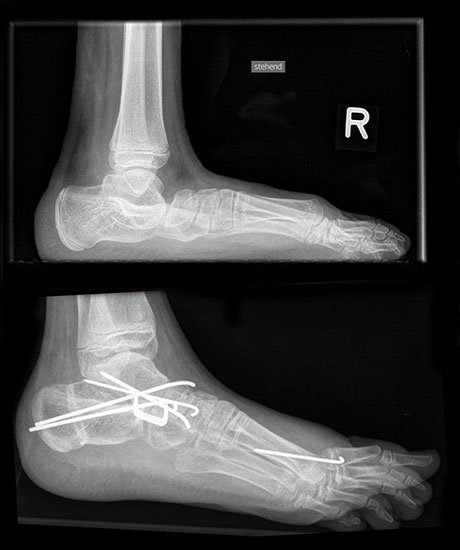

Bei jahrelanger Hackenfußfehlstellung sind teilweise auch knöcherne Korrekturen notwendig. Bei extrem fixierter Steilstellung des Calcaneus kommt es zu einem extremen Verlust des Hebelarms für die Wadenmuskulatur. Nur durch eine lateral-dorsal Verschiebung mit gleich­zeitiger Verkürzung der Wadenmuskulatur können dann die Hebelverhältnisse wiederher­gestellt werden. Häufig müssen solche Korrekturen mit einer komplexen Arthrodese von Rückfuß und Fußwurzel kombiniert werden um ausreichend stabile Verhältnisse zu erreichen. Gleichfalls sollten Varus- und Valgusdeformitäten durch Medial- oder Lateralverschiebung korrigiert werden 5.

Bei extremer Valgusdeformität des Rückfusses sollte das untere Sprunggelenk stabilisiert werden. Bei passiver Korrigierbarkeit bietet sich hierfür die Arthrorise an. Hierbei wird durch ein Implantat im Sinus tarsi die Rückfussvalgisierung blockiert. Nach Abschluss des Wachs­tums kann das Implantat wieder entfernt werden.

Bei kontrakter Fehlstellung des unteren Sprunggelenkes ist eine Arthrodese des Subtalar­gelenks indiziert (z.B. nach Green-Grice).

Gelingt es nicht die Dorsalextension über Sehnentransfers und ein Auftrainieren der Waden­muskulatur einzuschränken, besteht die Möglichkeit der ventralen Arthrorise mit Einbringen einem Knochenspan der auf der ventralen Tibia fixiert wird. Dieser wirkt als Stopper und blockiert die Dorsalextension in der gewünschten Gelenkstellung.